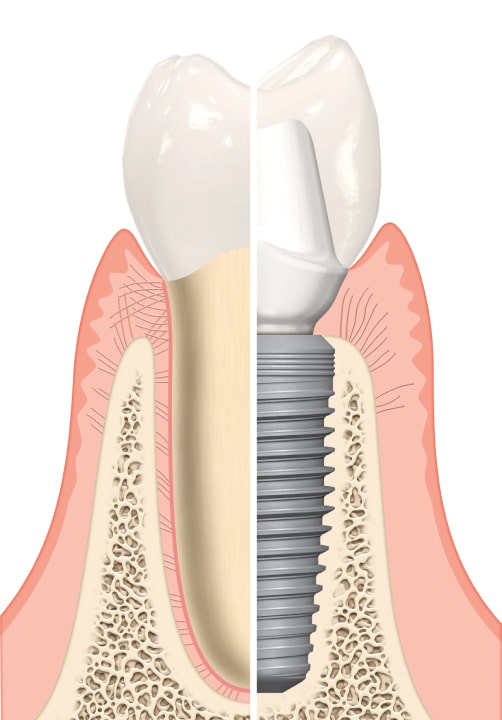

It is an artificial tooth root placed in the jawbone of the person in order to restore the function and appearance of the teeth with the right implant selection.

Since the implants fuse with your jawbone, they are permanent and you do not have to deal with constantly removing and replacing the prosthesis.